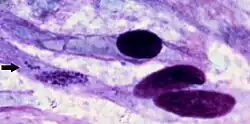

| Ehrlichia ruminantium bacteria within cell of brain of sheep that died of heartwater in Africa. | |

On post mortem examination, a light yellow transudate that coagulates on exposure to air is often found within the thorax, pericardium, and abdomen. Most fatal cases have the hydropericardium that gives the disease its common name. Pulmonary oedema and mucosal congestion are regularly seen along with frothy fluid in the airways and cut surfaces of the lungs. To definitively diagnose the disease, C. ruminantium must be demonstrated either in preparations of the hippocampus under Giemsa staining or by histopathology of brain or kidney.